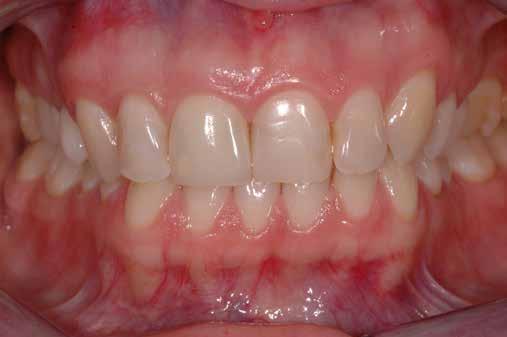

A 2020 januárjában elkezdett kezeléssorozat befejezését az év márciusában, hazánkba is begyűrűző Covid-19 pandémia késleltette, így kb. 6 hónap gyógyulás után láttunk hozzá az emergencia profil és a gingivális zenit ideiglenes koronával történő formázásához (11. és 12. kép). A 3 hetente végzett apró alakításokkal sikerült megfelelő ínyprofilt kialakítani, a „rózsaszín esztétika” a páciens számára is megfelelő volt. A bal felső nagymetsző fog meziális kompozit tömés cseréjét követően, individualizált nyitott kanalas lenyomati fejet készítettünk: az akrilát ideiglenes korona profilját átlátszó szilikonnal lemásoltuk, majd a körszimmetrikus gyári lenyomati fej és az ideiglenes korona kontúrja közötti hézagot folyékony kompozittal töltöttük ki (13. kép). Az így készített egyéni lenyomati fejjel vettünk lenyomatot a végleges, kerámialeplezésű cirkónium-dioxid vázas, átmenő csavaros rögzítésű koronához. (A fogtechnikai munkát Nébl Péter fogtechnikusmester készítette.), (14., 15., 16 és 17. képek).

A kész korona átadásakor a páciens elégedett volt az esztétikával, az azóta eltelt évben rendszeres kontrollokon jelent meg, melyek során meggyőződtünk a kemény- és lágyszövetek stabilitásáról (18. és 19. képek).